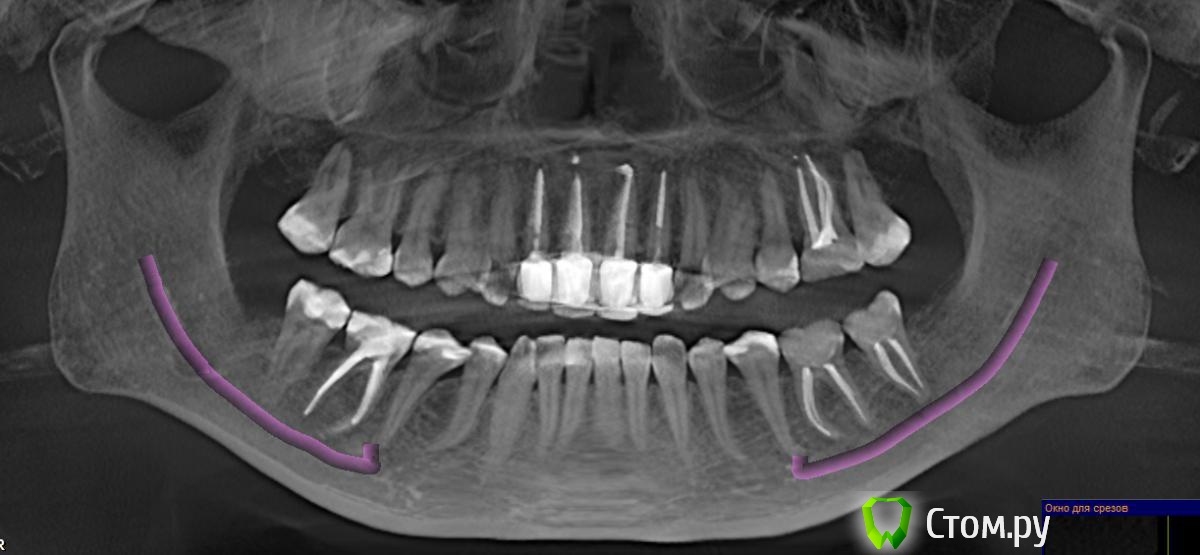

болел 6 или 7 зуб справа внизу (где-то между), боль не сильная была, ноющая, немного пульсирующая...иногда рядом чуть "дергала десна" (между 6 и 7). Болело месяцев 6 (то болит, то проходит). Ходила к стоматологам, промывали десневой карман, думали воспаляется десна, но нет, оказалось не она. Зуб 6 депульпирован давно (на снимке видно). Снимок прилагаю. 7-ка была живая с большой пломбой.

27 декабря депульпировали. Сильная боль ушла, НО осталось неприятное "пульсирование" и распирание в 6-м зубе! Причем такое ощущение, что зуб горячий (когда дотрагиваешься языком). И это уже точно 6-ка дает такие ощущения.

Это какой-то кошмар!!! Неужели на самом деле изначально проблема была в 6-м зубе? Он депульпирован давно.

Неужели причина мучения периодонтит 6-го зуба? Врачи говорят, что не он скорее всего...

Помогите найти причину боли и дискомфорта, пожалуйста!!! И что вообще скажете по снимку? Какие видно проблемы?